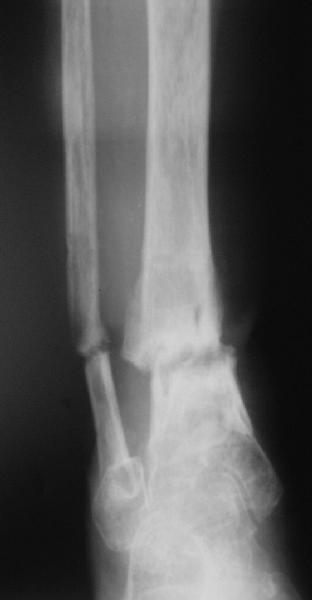

Еще несращение distal tibia |

Поступила женщина 72 лет. Полтора года назад - укушенная рана, перелом голени. Лечили аппаратом, не срослось. Долго не заживала рана.

Но вроде уже с полгода мягкие ткани закрыты. Спереди подпаянные рубцы. Есть приличная подвижность на уровне несращения. Картинки в приложении. Что предложите? Спсибо заранее.